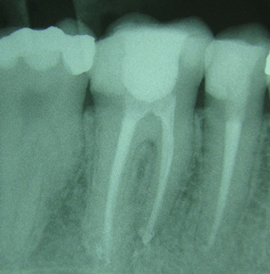

Ko bakterije najdejo svojo pot v notranjost zoba (bodisi zaradi kariesa, travme zoba ali globoke polnitve), pride do vnetne reakcije zobne pulpe (živca). Pogosto jo spremlja zelo močna bolečina. Včasih do odumrtja živca pride počasi in brez bolečin, ker okužba počasi napreduje. Bakterije v koreninske kanale napredujejo proti kosti in tam povzročijo vnetje (absces ali granulom).

Takšno stanje zoba zahteva endodontsko zdravljenje, ki preprečuje širjenje okužbe v kosti in na ta način ohranja zob in njegove korenine. Zdravljenja je potrebno izvajati pravilno, oziroma odstrani vzrok okužbe ter koreninske kanale očistiti in zapolniti v skladu s pravili stroke. Zato je treba vsako endodontsko zdravljenje preveriti z RTG posnetkom.

Koreninsko zdravljenje - endodontija

Postopek je popolnoma neboleč in ponavadi se konča pri drugem obisku. Sodobno zdravljenje kanalov je na nek način vrst mikrokirurškega posega in zahteva sterilno delovno področje. Vneto tkivo se odstranjuje ročno ali mehansko s sterilnimi instrumenti. Okužene kanale spiramo s tekočino za razkuževanje koreninskih kanalov, sušimo in zapolnimo z bioinertnim materialom. Rahla bolečina in občutljivost zob v naslednjih dveh do štirih tednih je normalna reakcija po endodontskem zdravljenju. To je obdobje, v katerem imunski sistem uničuje mogoče preostale bakterije. Endodontsko zdravljen zob ponavadi traja tako dolgo kot "živ" zob. Vendar pa se je treba zavedati, da je tak zob krhek in se zlahka zlomi, če je preobremenjen. Ker velika večina endodontski zdravljenih zob ima velike kariese ali večje zalivke, potrebno je narediti krono, ki bo zaščitila zob in zmanjšala možnost frakture. V zelo redkih primerih, endodontsko zdravljenje ne more biti uspešno izvedeno zaradi zelo tenkih in ukrivljenih kanalov ali slabega prejšnjega endodontskega zdravljenja. Nekateri od teh primerov se uspešno rešujejo z revizijo (ponovno čiščenje in razkuževanje kanalov) ali z apikotomijo (kirurško odstranitvijo vrška korenine).